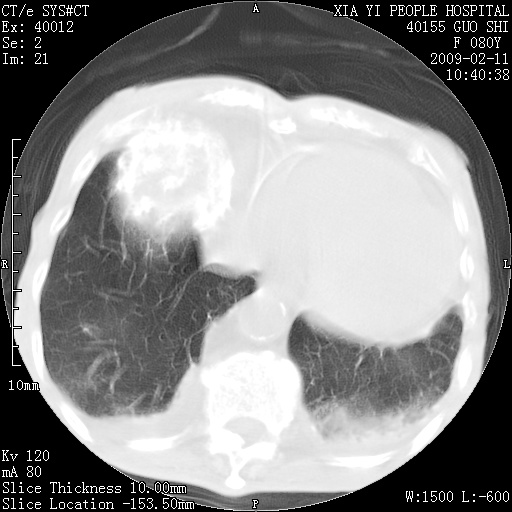

以下是引用随光逐影在2009-2-16 16:34:00的发言:[br]1)考虑右前纵隔皮样囊肿。2)双侧少量胸腔积液。

以下是引用zjzjr在2009-2-16 17:30:00的发言:[br]支持囊性畸胎瘤 双侧少量胸腔积液。